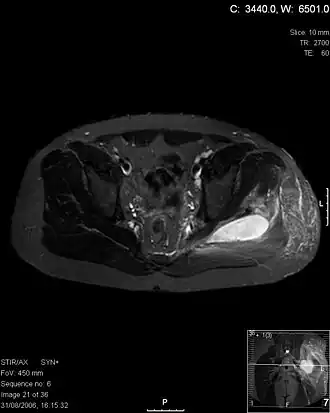

Transversale T2 MRI ter hoogte van de heup laat abcessen zien bij een pyomyositis-patiënt. | ||||

Pyomyositis, ook wel tropische pyomyositis of myositis tropicans, is een bacteriële infectie van de skeletspieren die resulteert in met pus gevuld abces. Pyomyositis komt vooral voor in tropische streken maar kan zich ook in gematigde streken voordoen.